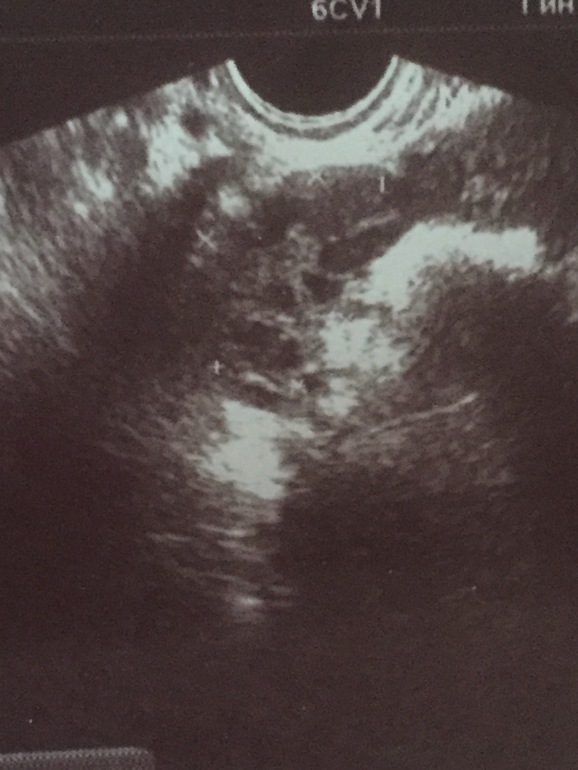

Была сегодня на УЗИ малого таза,врач говорит есть свободная жидкость в заднем своде в небольшом количестве.Спрашиваю значит прошла овуляция,говорит что да!

Потом говорит что она не видит доминантного фолликулах.

Говорит все чисто все хорошо,я спрашиваю ну Мои не овуляция что тогда раз болит и справа и слева иногда в ногу отдаёт.Говорит у вас поликистоз наверное...вообщем она сама не чего не знает,прикрепляю фото посмотрите